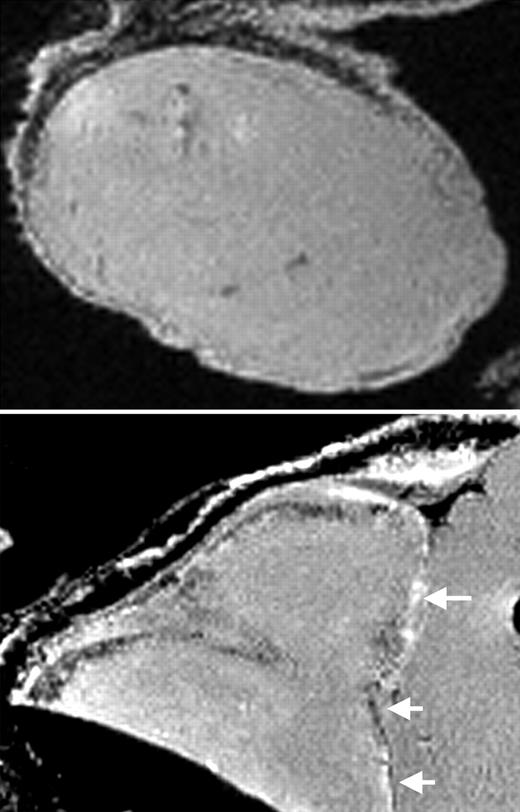

MRI of labeled CD34+ cells in tumors. See the complete figure in the article beginning on page 1217.